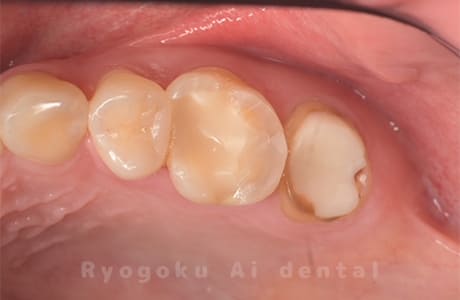

Case25

-

- 原因

- 重度カリエス

- 治療内容

- クラウンレングスニング治療

- 治療費用

- 44,000円×2

銀歯が取れたとのことでご来院された患者様です。歯の状態が悪いため、予後も考慮し、クラウンレングスニング治療を行い、被せ物の治療を今後行う予定です。

<リスク・副作用>

手術後は痛み、腫れ、痺れ、青あざなどの副作用が生じます。痛みは痛み止めを処方しますが、腫れ、青あざは1週間程度生じる場合があります。また、部位によっては神経の走行が複雑で、痺れが残り、長期的にお薬を処方する場合があります。